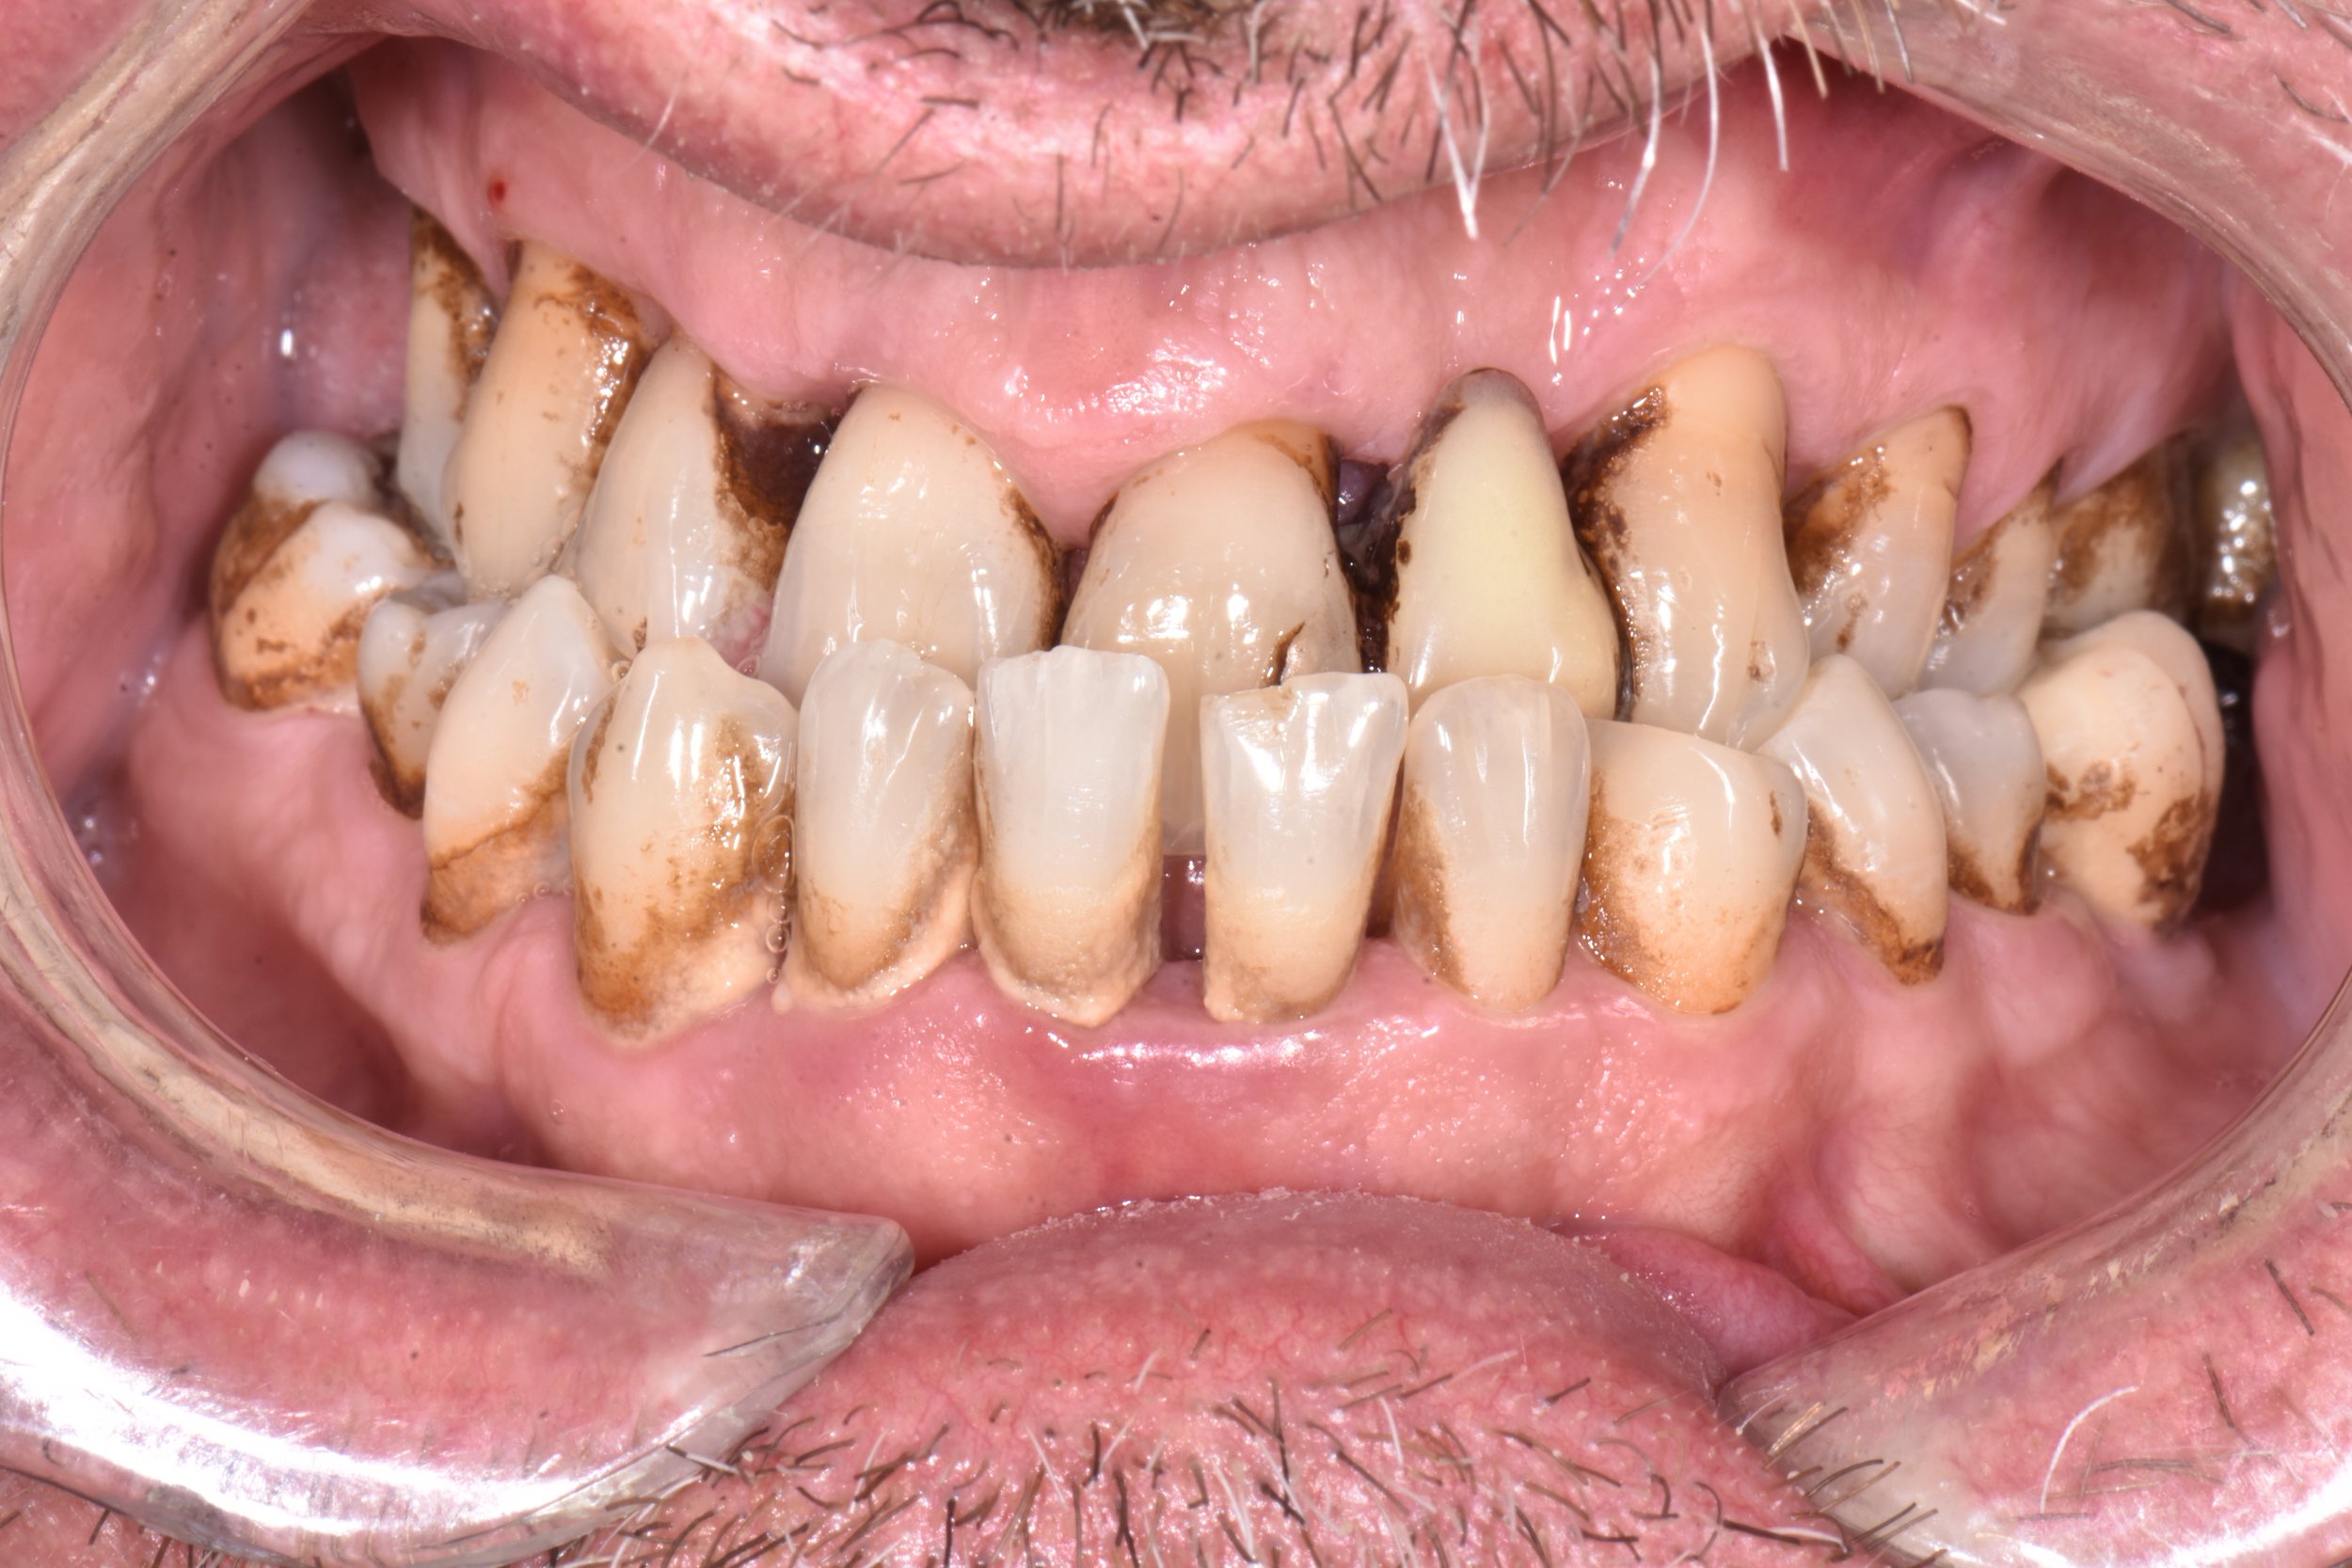

Les maladies parodontales sont des maladies inflammatoires chroniques d’origine infectieuses entrainant une perte des tissus de soutien de la dent, jusqu’à la perte de la dent.

C’est la présence de bactéries stagnantes autour des dents qui entraine, avec le temps, une inflammation de la gencive qui finit par créer une plaie qui s’infecte en profondeur.

Puis des plaques de tartre se créer le long des racines dentaires sous la gencive, ce qui maintien la plaie ouverte durant des années.

Très peu de symptômes sont ressentis. Il peut s’agir de saignements des gencives lors du brossage, de l’apparition d’espaces entre les dents, de dents qui se déplacent ou qui bougent, et ce, sans aucune douleur.